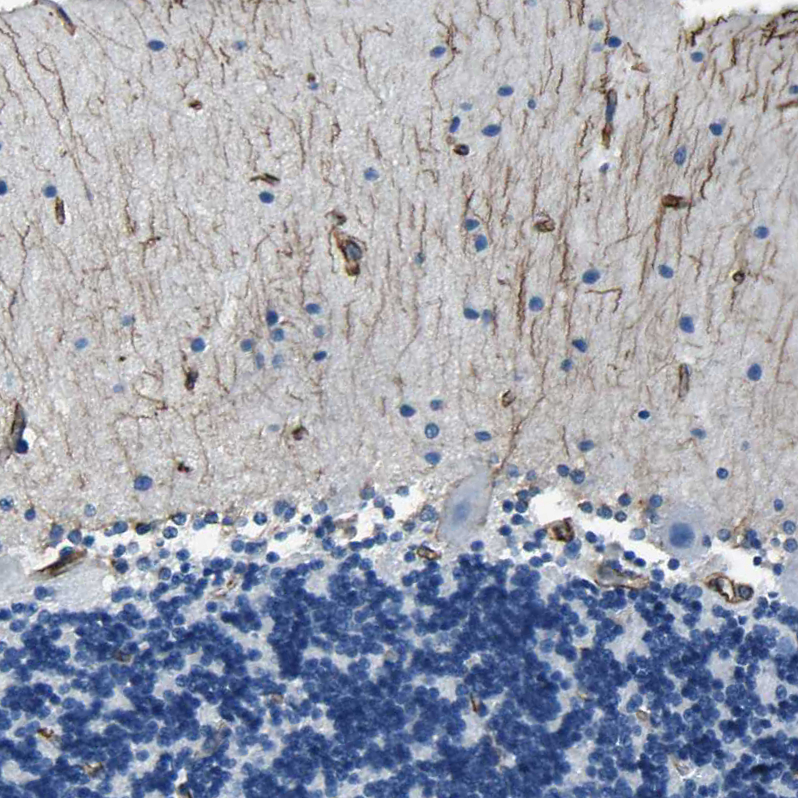

Immunohistochemical staining of human cerebellum shows moderate positivity in neuronal processes in molecular layer.